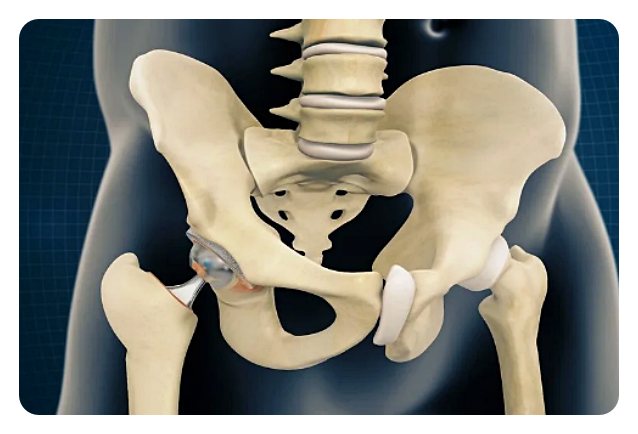

고관절은 몸을 지탱하고 움직이는 데 있어 중요한 부위 중 하나입니다. 이 관절은 골반과 대퇴골을 연결해주며, 우리가 걷고 뛰는 등의 일상생활을 가능하게 해줍니다. 하지만 때로는 다양한 이유로 이 고관절이 문제를 일으키게 됩니다. 이럴 때에는 고관절 수술이 필요하게 됩니다.

고관절 수술이란, 고관절이 다양한 이유로 손상되거나 질병에 걸려 그 기능이 제대로 작동하지 않을 때 이를 회복하기 위해 시행되는 수술입니다.

인공관절 치환술: 이 수술은 손상된 관절을 제거하고 그 자리에 인공 관절을 넣는 방식으로 이루어집니다. 인공관절은 대체로 금속, 플라스틱, 혹은 세라믹으로 만들어집니다.

특징: 인공관절 수술은 기본적으로 손상된 고관절을 제거하고 그 자리에 인공관절을 삽입하는 수술입니다. 이 인공관절은 금속, 플라스틱, 혹은 세라믹 등의 재료로 만들어져 있습니다.